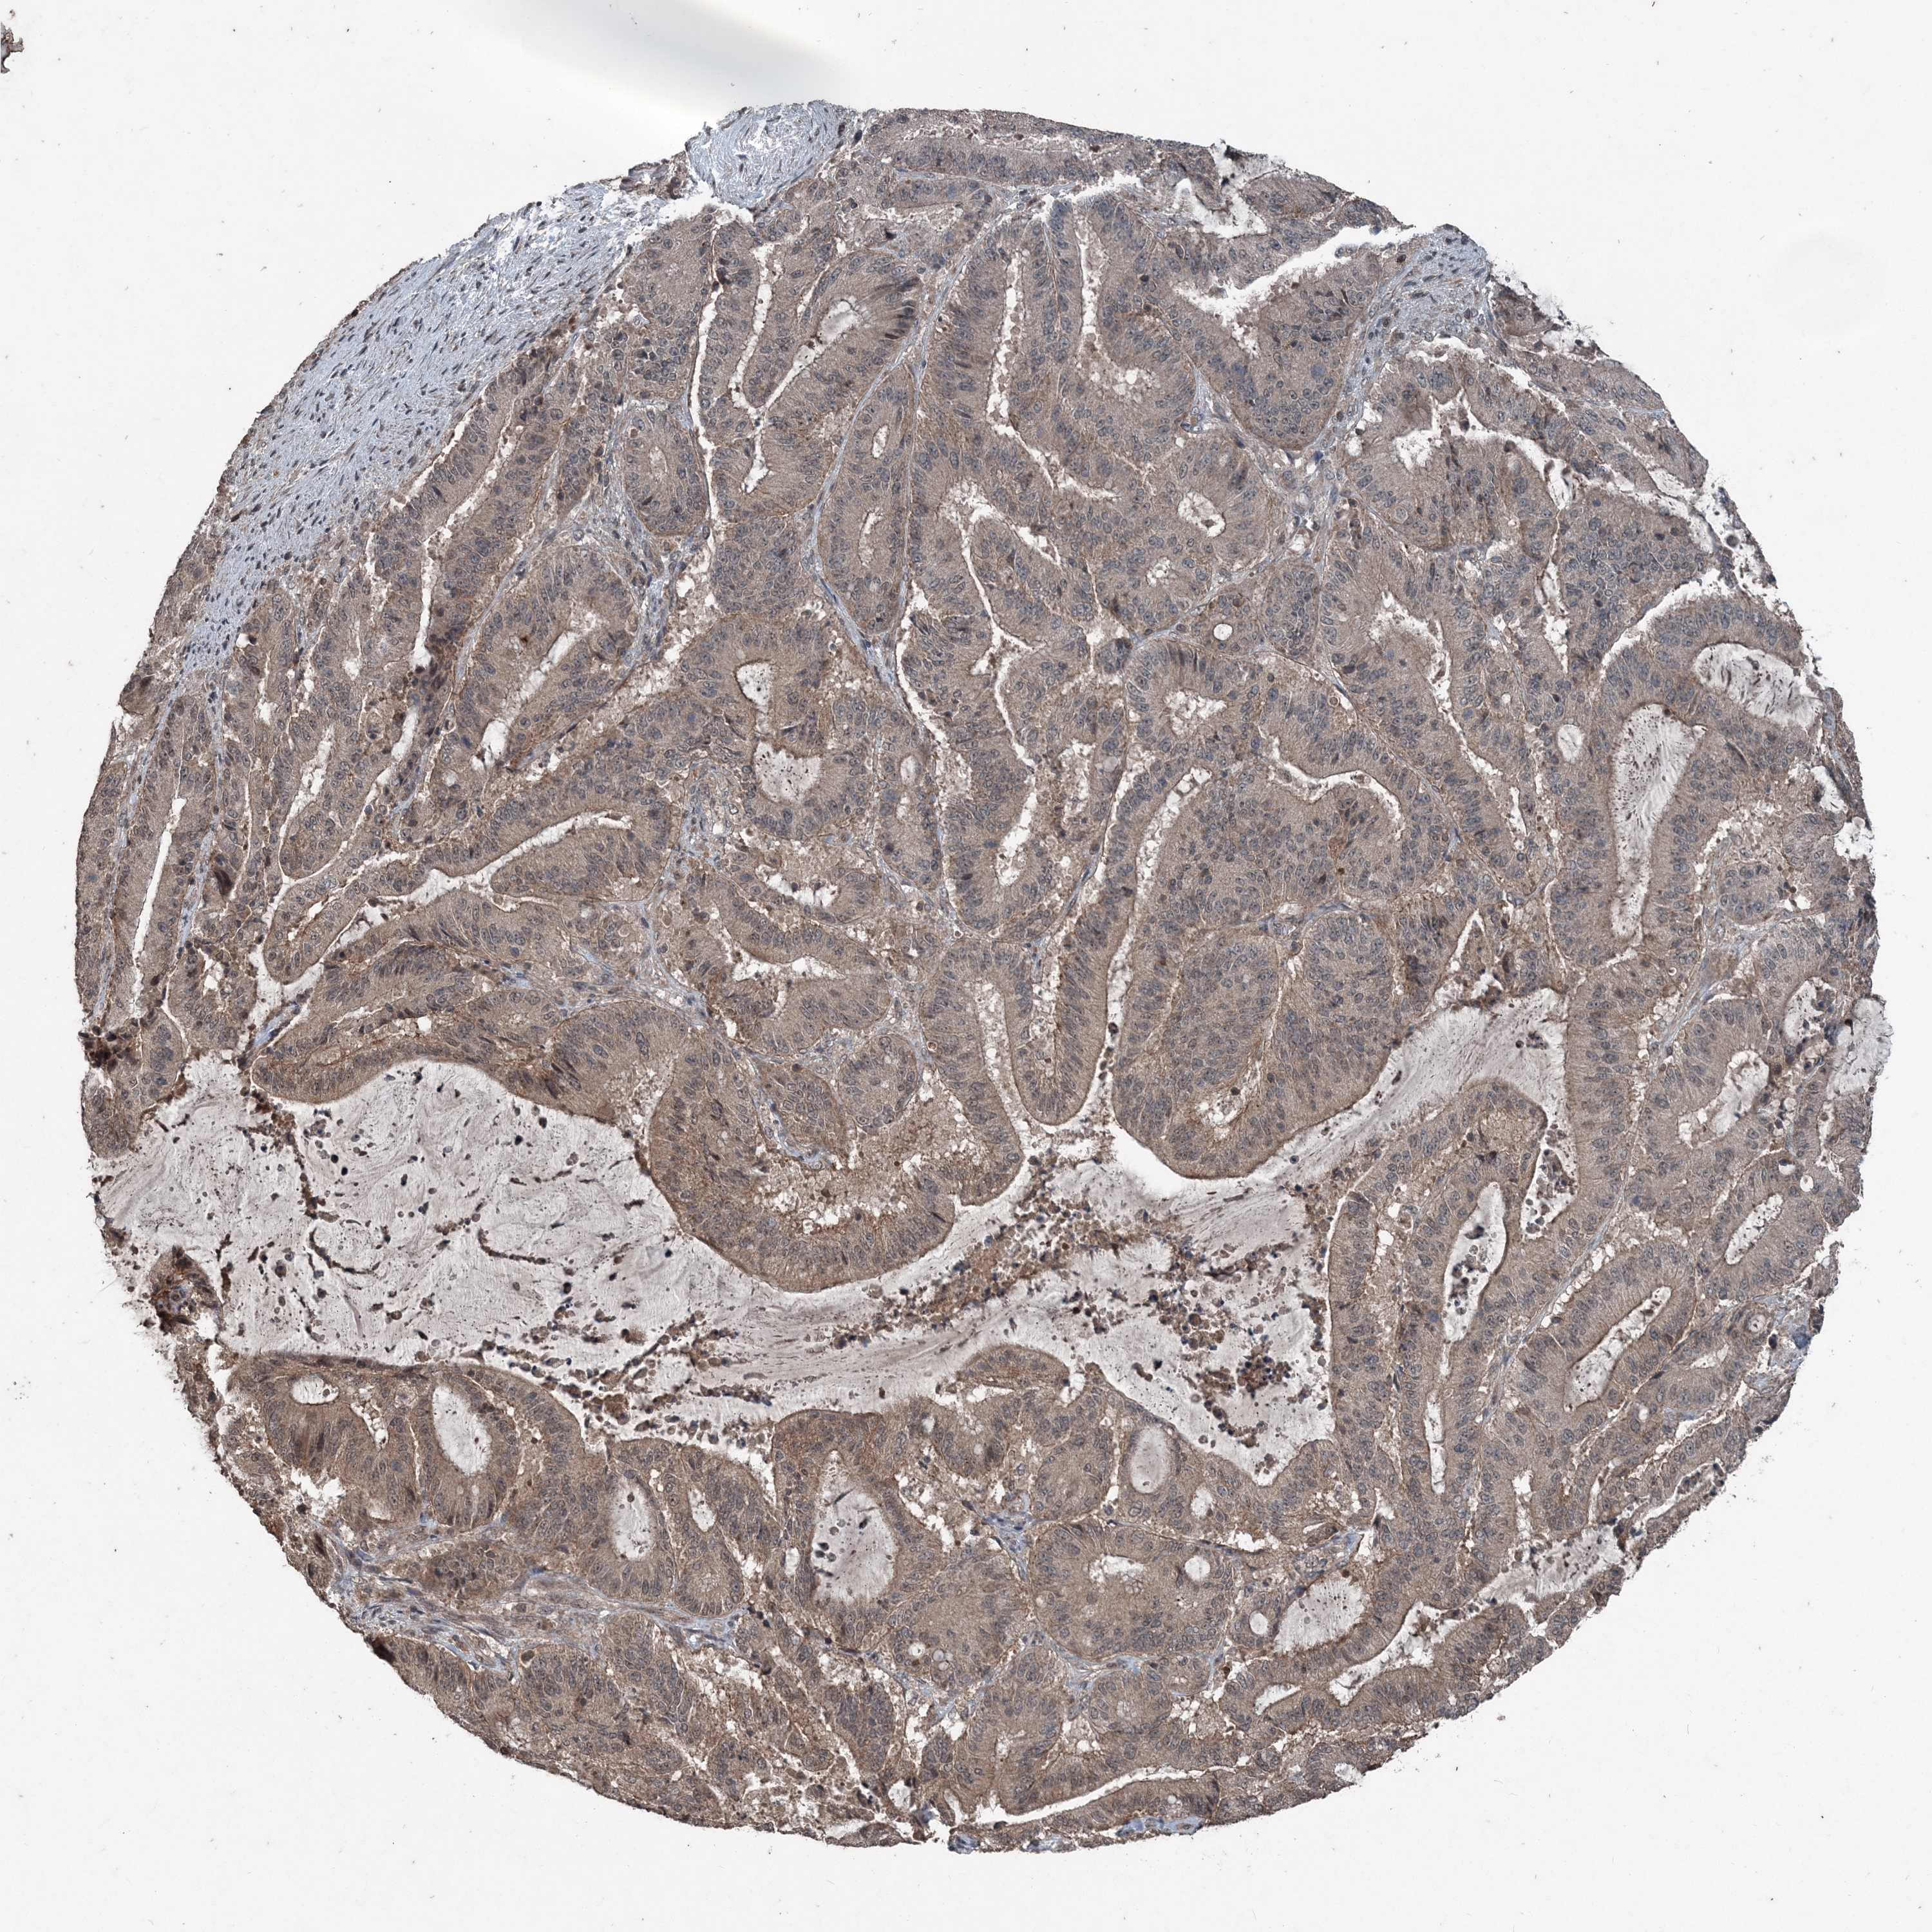

LIVER CANCER - Protein expressioni

A mouse-over function shows sample information and annotation data. Click on an image to view it in a full screen mode. Samples can be filtered based on level of antibody staining by selecting one or several of the following categories: high, medium, low and not detected. The assay and annotation is described here.

Note that samples used for immunohistochemistry by the Human Protein Atlas do not correspond to samples in the TCGA dataset.

Antibody stainingi

Antibody staining in the annotated cell types in the current human tissue is reported as not detected, low, medium, or high, based on conventional immunohistochemistry profiling in selected tissues. This score is based on the combination of the staining intensity and fraction of stained cells.

Each image is clickable and will lead to virtual microscopy that enables deeper exploration of all samples and also displays staining intensity scores, fraction scores and subcellular localization as well as patient and tissue information for each sample.

Antibody CAB033687

Cholangiocarcinoma

Carcinoma, Hepatocellular, NOS